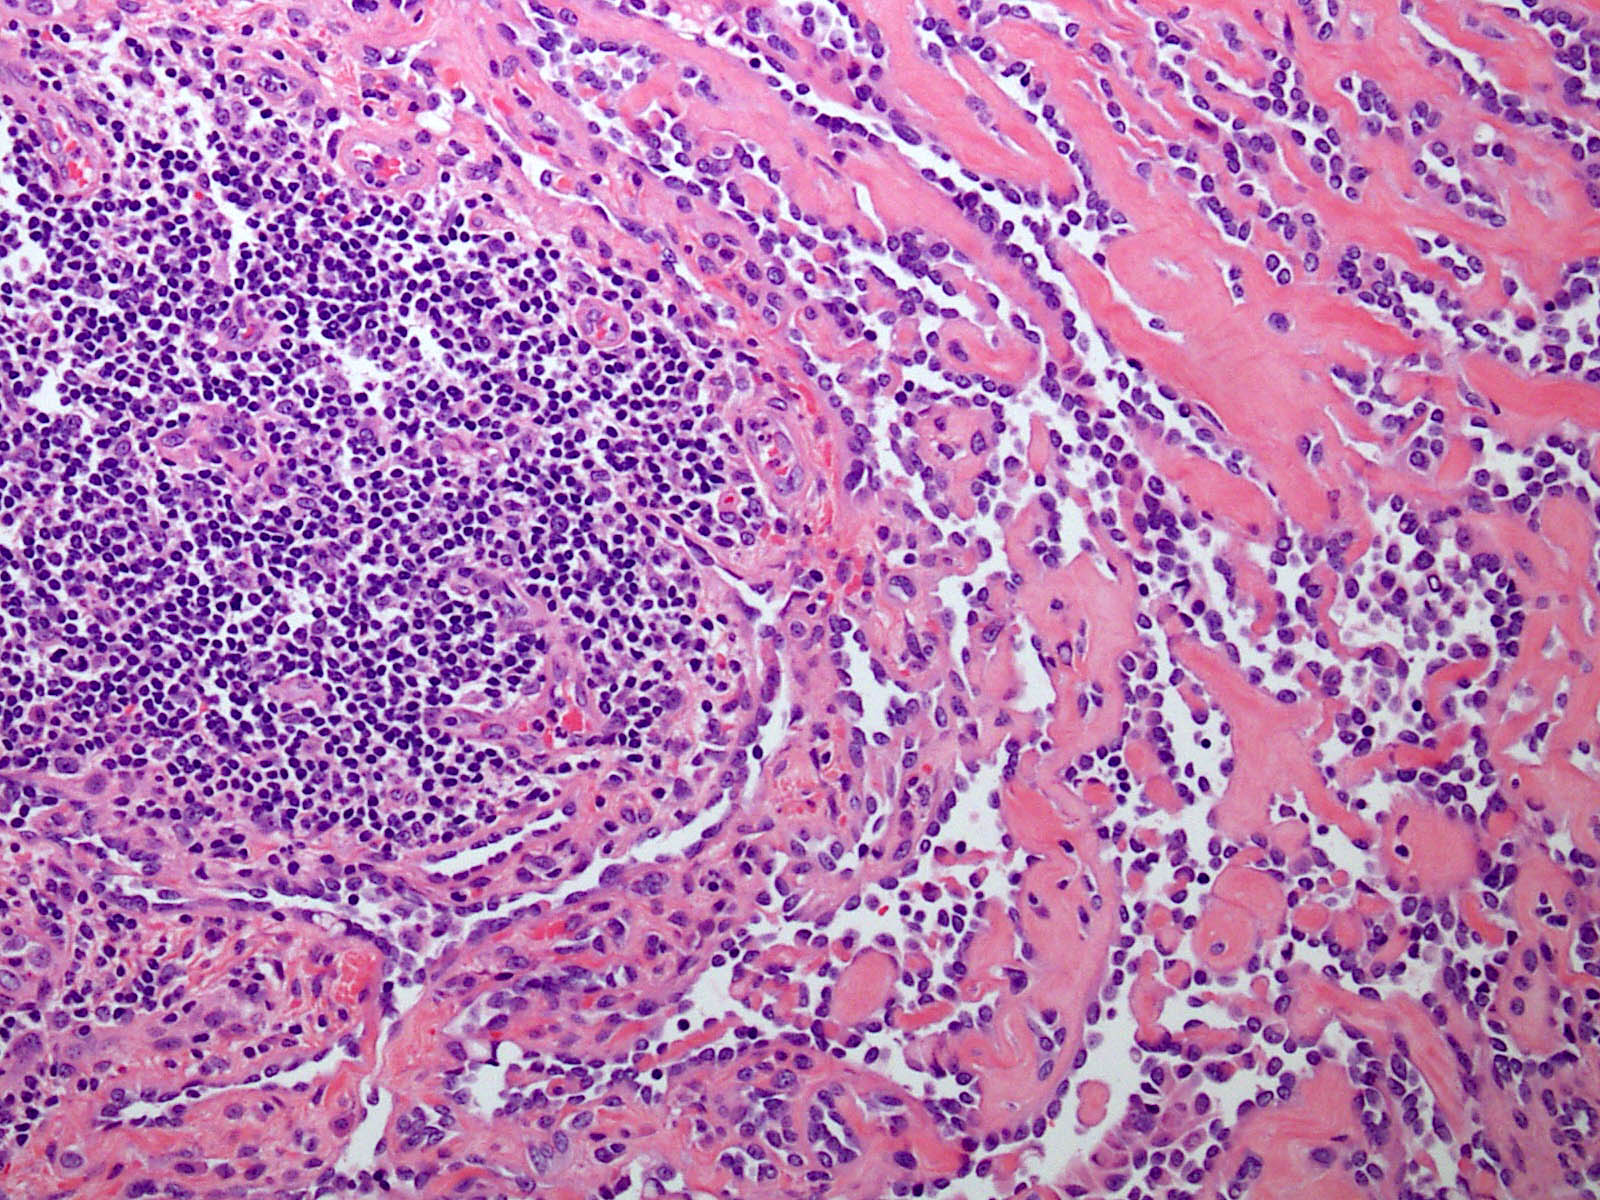

Microscopic (histologic) description

- Poorly circumscribed lesion, infiltrating dermis and subcutis with dissecting planes (Int J Clin Exp Pathol 2010;3:528)

- Composed of elongated arborizing vascular channels that resemble rete testis, hence the name

- Endothelial cells are bland with hobnailed hyperchromatic nuclei

- Nuclear atypia is not seen

- Mitotic figures are rare

- Lesional stroma is fibrotic and shows lymphoid infiltrate (J Med Case Rep 2021;15:69, Int J Clin Exp Pathol 2010;3:528)

- Occasional solid growth may be seen (Stockman: Diagnostic Pathology - Vascular, 1st Edition, 2015)

- In the dermis, vessels may become ectatic and lose retiform appearance

- Occasional cells with cytoplasmic lumina may be rarely seen (J Med Case Rep 2021;15:69)

- Occasionally, intraluminal papillary proliferation may be seen, resembling Dabska tumor (Hornick: Practical Soft Tissue Pathology - A Diagnostic Approach, 2nd Edition, 2018)

A 30 year old man presents with a red to purple plaque involving the right thigh. A punch biopsy through the lesion shows light microscopic features as depicted in the photomicrograph above. Which of the following is the most likely diagnosis in this case?

E. Retiform hemangioendothelioma. The photomicrograph shows a vascular lesion with retiform vessels lined by a single layer of endothelial cells with hobnailing. A lymphoid aggregate is also present. Answers B - D are incorrect because other characteristic essential features of any of the given options, except atypical vascular lesion, are not seen here. Answer A is incorrect because the clinical scenario is not appropriate for a diagnosis of atypical vascular lesion. Therefore, the correct diagnosis is retiform hemangioendothelioma.